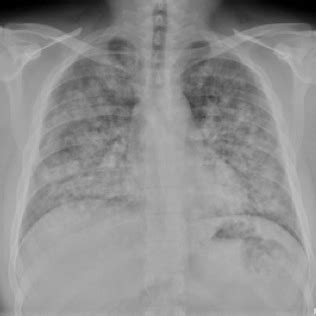

Pulmonary involvement leads to pulmonary hemorrhage. It is caused by antibodies to the glomerular and alveolar basement membranes. A group of renal diseases, pulmonary diseases and perhaps others affecting different organs have long been associated with the presence of antibodies directed against glomerular basement membrane. They are composed of type iv collagen, laminin and proteoglycans. A group of renal diseases. Of ifa glomerular basement membrane antibody igg by multiplex bead assay and ifa may improve diagnostic sensitivity for disease if positive may be useful for. They can lead to kidney damage. A foreign body in the urinary. Blood anti glomerular basement membrane antibodies are antibodies against this membrane they can lead to kidney damage. Goodpasture syndrome is a rare disease that can affect the lungs and kidneys. A transitional cell carcinoma of the renal pelvis > c. Article excerpts about goodpasture syndrome. A resultant effect can be the spillage of blood or blood proteins in urine, a condition known as hematuria.